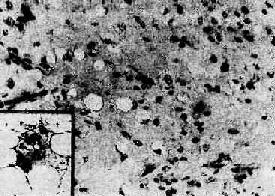

图7-18 脂肪肉瘤

瘤细胞分散,胞浆内含大小不等的脂肪空泡。瘤细胞间有多量粘液性基质(图中呈灰色),并见瘤巨细胞(插入图)